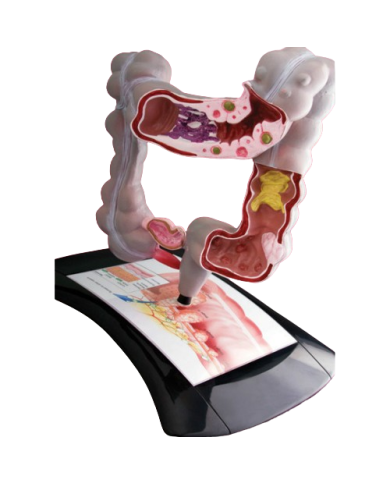

Modello anatomico PER FORNITURE CASE FARMACEUTICHE

Modello anatomico PER FORNITURE CASE FARMACEUTICHE

Modello anatomico PER FORNITURE CASE FARMACEUTICHE

Modello anatomico PER FORNITURE CASE FARMACEUTICHE

Modello anatomico PER FORNITURE CASE FARMACEUTICHE

Modello anatomico PER FORNITURE CASE FARMACEUTICHE

Modello anatomico PER FORNITURE CASE FARMACEUTICHE

Modello anatomico PER FORNITURE CASE FARMACEUTICHE

Modello anatomico PER FORNITURE CASE FARMACEUTICHE

Modello anatomico PER FORNITURE CASE FARMACEUTICHE

Modello anatomico PER FORNITURE CASE FARMACEUTICHE

Modello anatomico PER FORNITURE CASE FARMACEUTICHE

Modello anatomico PER FORNITURE CASE FARMACEUTICHE

Modello anatomico PER FORNITURE CASE FARMACEUTICHE

Modello anatomico PER FORNITURE CASE FARMACEUTICHE

Modello anatomico PER FORNITURE CASE FARMACEUTICHE

Modello anatomico PER FORNITURE CASE FARMACEUTICHE

Modello anatomico PER FORNITURE CASE FARMACEUTICHE

Modello anatomico PER FORNITURE CASE FARMACEUTICHE

Modello anatomico PER FORNITURE CASE FARMACEUTICHE

Modello anatomico PER FORNITURE CASE FARMACEUTICHE

Modello anatomico PER FORNITURE CASE FARMACEUTICHE